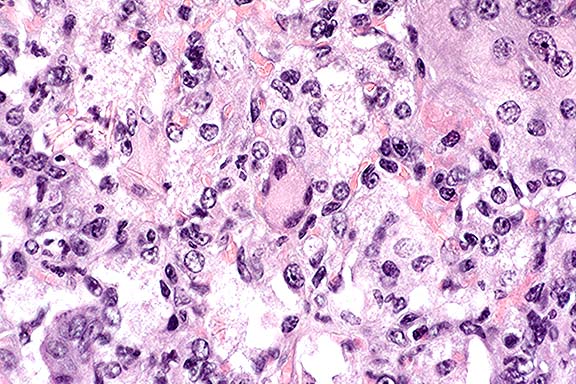

Case 3-2. Dermis. Macrophages with multinucleated giant cells, neutrophils and budding Sporothrix schenkii yeast. PAS 40X

AFIP Diagnoses: 1. Haired skin: Pyogranuloma, with multifocal moderate pyogranulomatous lymphangitis and mild superficial perivascular lymphohistiocytic and eosinophilic dermatitis, burro, equine. 2. Haired skin, dermal histiocytes and multinucleated giant cells: Intracytoplasmic eosinophilic spicular structures.

Conference Note: Special stains performed at the AFIP demonstrated rare round to oval 5-7µm yeasts compatible with Sporothrix schenkii. Most conference participants noted eosinophilic intracytoplasmic structures in histiocytic cells; however, they are suspected to be protein crystals.